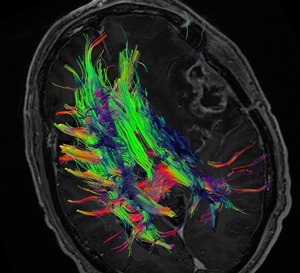

Diagnostic Radiology Neuroradiology DTI Image A

How it works:The white matter is the wiring of your brain. This wiring delivers the electrical signals from your cortex to your extremities. Diffusion Tensor imaging or DTI, uses the magnetic properties of water to create a map of the white matter in the brain. This data can be modeled into a 3 dimensional map of the white matter called tractography.

Equipment: Our MRI suite uses the latest Phillips 3.0 tesla magnet coupled with a state of the art Dynasuite post processing system. Our exams are personally tailored and monitored by a CAQ board certified neuroradiologist.

Diagnostic Radiology Neuroradiology DTI Image B

Benefits: DTI is used for presurgical and preradiation planning for an intracranial lesion that could potentially involve eloquent cerebral cortex. The DTI exam is tailored to the location of the lesion and the normal brain adjacent to it. The goal is to allow the neurosurgeon to plan the optimal, least invasive approach to a lesion, and to allow the surgeon to more completely excise the mass or lesion while preserving as much normal function as possible. DTI also allows a patient to better understand the potential risks of having surgery. Our neurosurgical colleagues at OHSU integrate the DTI information into the operating suite using a 3D stereotactic software so they can see the location of the white matter tracts during the surgery. Many studies have shown improved morbidity and increased survival rates in patients who have had preoperative DTI.

Diagnostic Radiology Neuroradiology DTI Image C

Exam Preparation: The technologist will interview you prior to scan to make sure you have no contraindications to being in the MRI scanner. Patients with braces or other metal near the head or neck may not be suitable for DTI because of the artifacts the metal can cause. The exam is usually done in conjunction with a functional MRI (FMRI).

What to expect: DTI alone takes approximately 2-6 minutes of scanner time. During this time it is very important to remain still. The post-processing of the data by the neuroradiologist can take up to 1 hour. The DTI is usually done along with an FMRI examination.

Content by Dr. Jeffrey Pollock

Diffusion Tensor Tractography MRI Image for Radiology

How it works: The white matter is the wiring of your brain. This wiring delivers the electrical signals from your cortex to your extremities. Diffusion Tensor imaging or DTI, uses the magnetic properties of water to create a map of the white matter in the brain. This data can be modeled into a 3 dimensional map of the white matter called tractography.

Equipment: Our MRI suite uses the latest Phillips 3.0 tesla magnet coupled with a state of the art post processing system. Our exams are personally tailored and monitored by a CAQ board certified neuroradiologist.

Benefits: DTI is used for presurgical and preradiation planning for an intracranial lesion that could potentially involve eloquent cerebral cortex. The DTI exam is tailored to the location of the lesion and the normal brain adjacent to it. The goal is to allow the neurosurgeon to plan the optimal, least invasive approach to a mass, and to allow the surgeon to more completely excise a mass while preserving as much normal function as possible. DTI also allows a patient to better understand the potential risks of having surgery. Our neurosurgical colleagues at OHSU can integrate the Tractography information into the operating suite using a 3D stereotactic software so the surgeons can see the location of the white matter tracts during the surgery. Many studies have shown improved morbidity and increased survival rates in patients who have had preoperative DTI.

What to expect: DTI alone takes approximately 6 minutes of scanner time. During this time it is very important to remain still. The post-processing of the data to generate the trachtography by the neuroradiologist can take up to 1 hour. The DTI is usually done along with an FMRI examination.

Created by Dr. Jeffrey Pollock